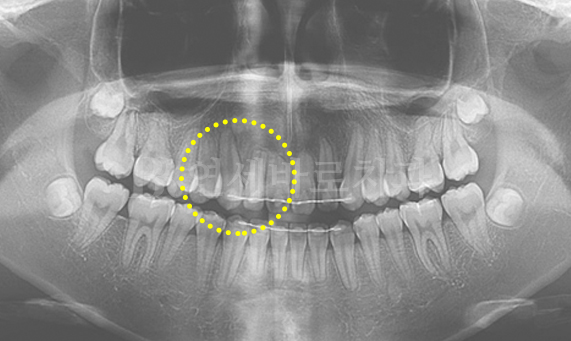

매복치

매복치는 여러 가지 원인에 의하여 치아가 나와야 할 시기가 지나도록 잇몸 안에서 못 나오고 있는 것을 말합니다. 좌우 치아가 나는 시기가 6개월 이상 차이가 나면 한 번쯤 치과에서 방사선 사진 촬영 검사를 받아볼 필요가 있습니다.

매복치 교정 CASE

-